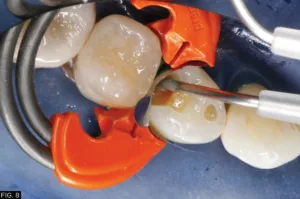

A young female physician presented to my office with a chief complaint of sensitivity to cold and sweets in her lower right dentition which has been persistent for approximately 1 month. Upon clinical and radiographic examination, it was determined that her lower right first premolar #28 (#44) had a previous restoration that had fractured and was compromised by recurrent caries. (FIG. 1)

The carious lesion was rather deep into the tooth according to the radiographic image but not wide. The carious lesion was less than ½ the distance between the buccal/lingual cusp distance making this an excellent case for a direct composite restoration. (FIG. 2)